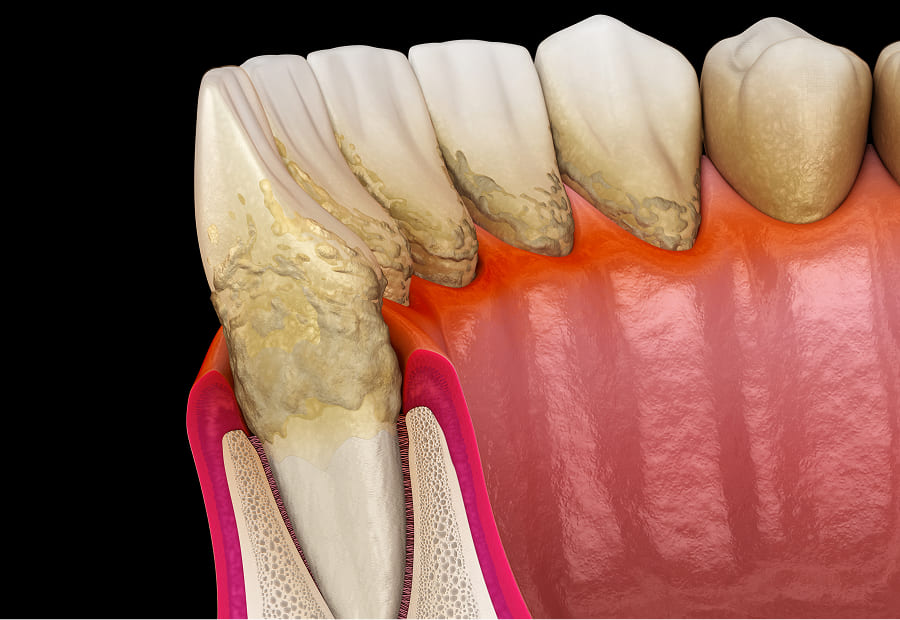

歯周病は細菌感染によって歯の周りの組織が破壊され、最悪の場合は歯が抜け落ちてしまう疾患です。初期段階では自覚症状が出にくい特徴があるため、異変を感じたらすぐに治療を受けることが大切です。当院では、治療前に検査を実施して歯周病の原因・進行度を診断し、治療計画を立てて治療を進めていきます。

歯周病が及ぼす全身への影響

歯周病はお口の中だけの病気だと思っていませんか?歯周病はお口の中だけでなく、全身に影響を及ぼす恐ろしい病気です。

歯周病菌によって深い歯周ポケットが作られると、そこから細菌や病原菌が歯肉の血管を通じて血液に流れ込みます。

これによって全身に運ばれ、組織や臓器に影響を及ぼしてしまうと考えられています。

近年ではさまざまなリスクが明らかになっており、以下のような全身疾患との関わりが分かっています。

日本人の成人の多くの人がかかっていると言われる歯周病は、治療が遅れるほど負担が大きくなります。

歯周病治療は、はじめに口腔内の状態を診査し、その結果をもとに治療方針を説明。患者さんの理解、同意を頂いてから治療を開始します。

治療では必要に応じ排膿や噛み合わせの調整などの応急処置を施し、その後はプラークコントロールやスケーリングなどを行い歯茎の健康を取り戻していきます。